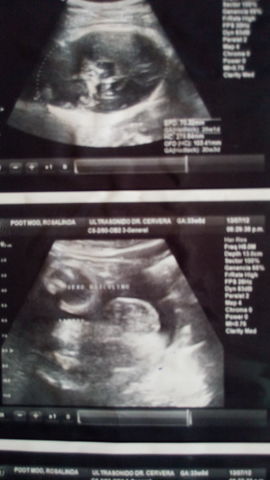

• Gestación

Gestación

Tengo seis meses de haberme concebido mis padres, ya tenía un peso de 600 g aproximadamente, mi piel estaba arrugada y mi cabeza aún está muy grande con el resto de mi cuerpo. Si naciera en es ese momento podría morir.

(Ultrasonido, estoy en la panza de mi mamá)